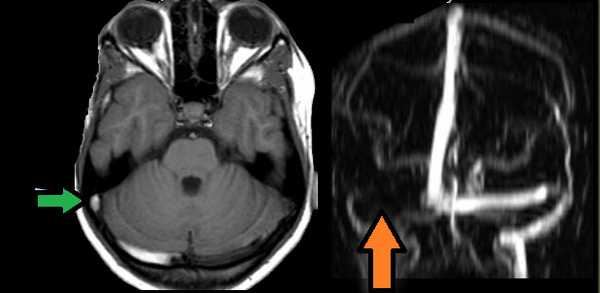

МРТ головного мозга: справа (зеленая стрелка) на Т2-взвешенном изображении отмечается имеющийся в норме феномен «пустоты потока» от правого сигмовидного синуса и яремной Вены. Слева (оранжевая стрелка) отмечается аномально высокий сигнал, в результате, вероятнее, тромбоза. Для подтверждения синус-тромбоза и окончательного определения локализации и протяженности тромбоза необходимо проведение МР-венографии.

МР-венография: тромбоз левого поперечного синуса. Отмечается потеря МР-сигнала от левого поперечного синуса.

Наличие визуализации синуса на «сырых» данных или же МРТ головного мозга подтверждает тромбоз синуса и исключает его гипоплазию.

МР-венография: тромбоз правого поперечного синуса. Отмечается потеря МР-сигнала от правого поперечного синуса.

Наличие визуализации синуса на «сырых» данных или же МРТ головного мозга подтверждает тромбоз синуса и исключает его гипо- и аплазию.

Тромбоз правого поперечного синуса. Отсутствие феномена «пустоты потока» от правого поперечного синуса на МРТ головного мозга. Отсутствие визуализации правого поперечного синуса на МР-венографии.